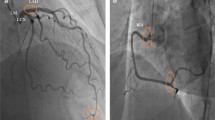

Coronary angiography protocols

CSF was defined according to the thrombolysis in myocardial infarction (TIMI) frame count (TFC) method. Coronary angiogram was performed using a digital subtraction angiography system (Allura Xper FD20; Philips Medical Systems, Best, the Netherlands), which used the standard Judkins technique to obtain images at the rate of 30 frames/s. The injection rate was 4–5 ml/s in the left coronary artery and 3–4 ml/s in the right coronary artery (RCA). The left coronary artery was injected with 8-10 ml contrast agent and RCA was injected with 6-8 ml contrast agent. The left anterior descending coronary artery (LAD) was imaged as the right anterior oblique projection with an angle of 20–25°, the left circumflex coronary artery (LCX) was imaged as the right anterior oblique projection with an angle of 20–25°, and the RCA was imaged as the positive projection with an angle of 30°. The first frame was defined when the contrast agent touched two medial walls of the coronary artery and advanced steadily with a diameter of more than 70%, and the last frame was defined when the leading edge of the contrast agent reached the end of the branches of the coronary artery. The frame counts in the LAD were divided by a factor of 1.7 to correct for its longer length. According to Gibson et al., any frame count over 27 is considered abnormal and indicates significant CSF [17]. All patients were carefully monitored for pulse and blood pressure during coronary angiogram.

Lp-PLA2 levels in the CSF group were significantly higher than those in the control group (288.6 ± 50.3 versus 141.9 ± 49.7, P < 0.001) (Table 1,Fig. 1). The TFC values of the two groups of coronary arteries were calculated respectively. The mean TFCs of LAD, LCX and RCA were significantly higher in CSF patients than in NCF patients (p < 0.001 for each coronary artery, Table 2, Fig. 2).